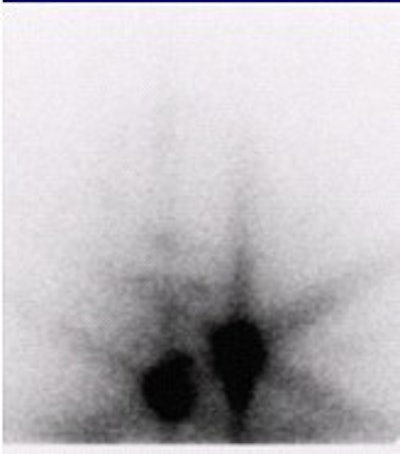

![]() |

| Fifty-three-year-old male with papillary carcinoma who underwent total thyroidectomy. First post-operative scan with 5 mCi 131I at 72 hours. Two foci of remnant metastases are seen. |

| Four weeks later, a scan with 100 mCi 131I at 72 hours was obtained. The stunned lesions failed to take up any of the therapy dose. |

| At one-year follow-up on 5 mCi 131I scan at 72 hours, the same two lesions are present. Images courtesy of Dr. Hee Myung Park. |